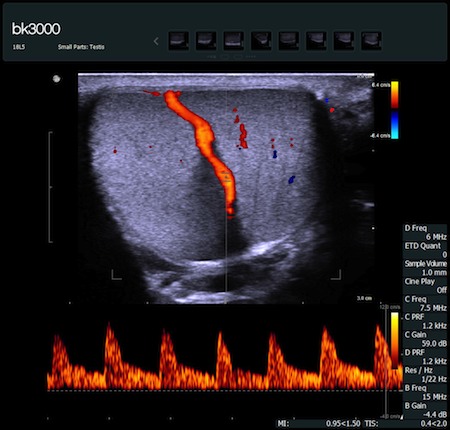

Obrazy kliniczne uzyskane aparatem bk3000

Fot. Tętnica jądrowa - obraz uzyskany głowicą 18L5 - opcja PW Doppler.